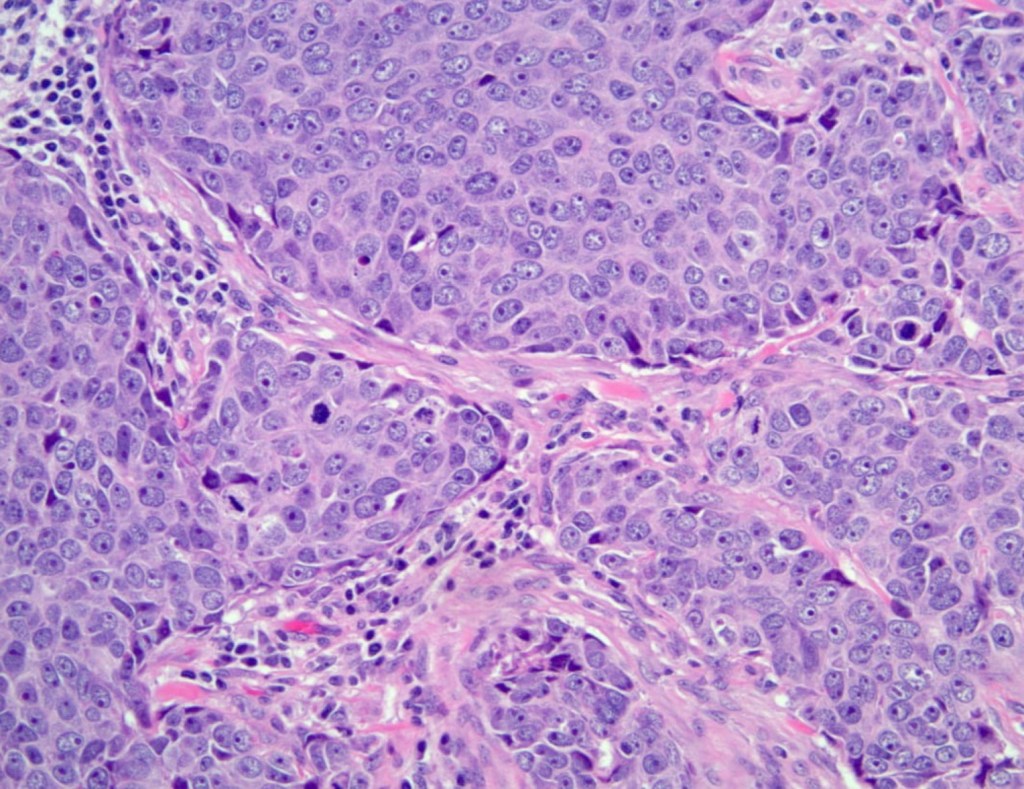

- Histologically, TNBCs are most often of:

- Higher grade

- Exhibit tumor necrosis

- Have more frequent nodal metastases

- The majority of TNBCs are of:

- Invasive ductal breast cancer, no special type:

- Characterized by:

- High mitotic indices

- Presence of central necrotic or fibrotic zones

- Pushing borders

- Conspicuous lymphatic infiltrate

- Typical or atypical medullary features